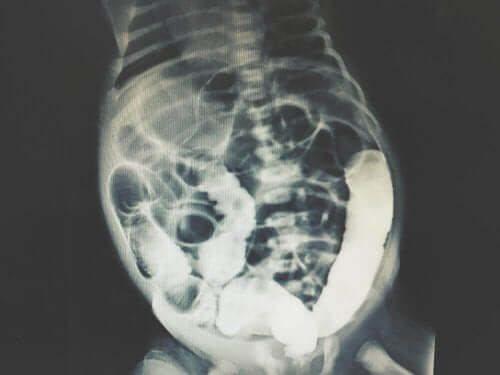

Afhankelijk van de resultaten kan men de oorzaak van de buikproblemen bepalen. Ze kunnen ook testen uitvoeren om inwendige afbeeldingen van de buik te krijgen. Op deze manier kunnen ze de diagnose vergemakkelijken.